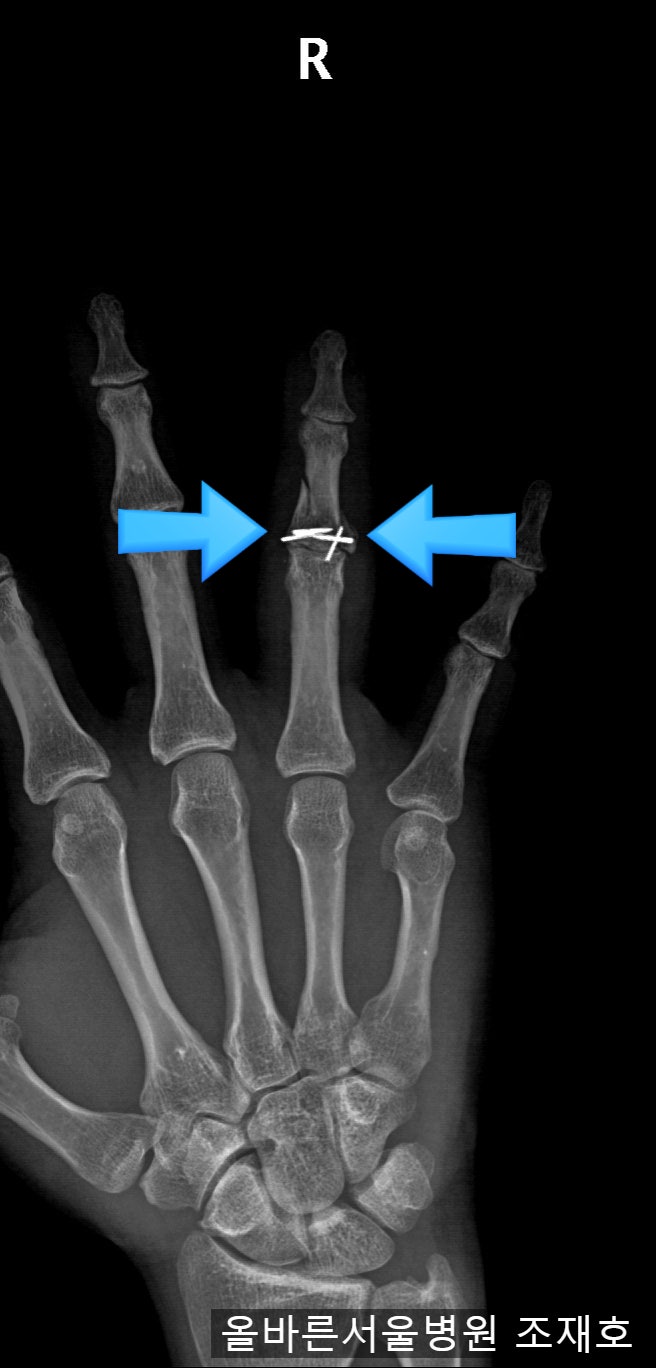

손가락이 움직이지 못하고 점점 뻣뻣해지고 관절 사이의 거리가 점점 좁아집니다. 뼈(파란색 화살표)가 나오고 있는데 관절이 좋지 않고 연골이 점점 손상되고 있는 것 같습니다(흰색 화살표). 수술 6개월 후 사진에서는 관절이 심하게 손상되어 새끼손가락까지 변형되어 외상성 관절염이 빠르게 진행되어 거의 모든 관절이 파괴되었습니다. 계속 관찰하였으나 관절염이 호전되지 않고 통증이 심해지며 관절의 운동범위가 감소하였다. 병원에서는 외상성 관절염이 너무 심해서 X-ray로는 안보이는 실리콘 인공관절을 해줬습니다. 이전에는 뼈가 관절염에 밀착되어 있었지만 실리콘 관절이 들어오면서 조금씩 뼈가 분리되는 것을 볼 수 있습니다. 이후 시간이 지남에 따라 실리콘 조인트 삽입으로 약간 넓어졌던 조인트 간격이 다시 좁아지는 것을 볼 수 있었다. 실리콘 인공관절 후 1년은 뼈가 다 붙고 딱딱해져서 손가락을 전혀 움직일 수 없었습니다. 이 경우 인정되었습니다. 둘째, 손가락을 움직일 수 없어 매우 불편하다 손을 펼 때 자신도 모르게 손을 치거나 누르면 손을 닫은 채로 있어야 한다. 그래서 인공적으로 열분해탄소를 사용하기로 하고 관절을 재수술하게 되는데 수술 중에는 인공관절을 위한 공간을 확보하기 위해 뻣뻣한 손가락 관절을 먼저 제거해야 합니다. 안에 있는 실리콘 커넥터를 제거합니다. 수술중에 잘려나갔지만 원래는 일체형으로 되어있어 가동관절이 아니고 실리콘이 부드러워서 손가락을 구부리면 휘어져서 계속 움직이는데 뼈가 부드럽다면 이렇게 붙여도 소용없다. 열분해 탄소 관절을 위한 공간을 확보하고 근위 지골에 파일을 사용하여 보철 관절이 삽입될 공간을 확보합니다. 파일은 인공 관절의 방향 및 회전 정렬을 모두 고려합니다. 그것이 골수 구멍에 있는지 측면에서 확인하십시오. 인공관절 검사기를 삽입하여 삽입할 인공관절의 크기와 방향, 인대의 균형을 확인합니다. 측면에서 핏을 확인하고 실제 인공관절을 삽입합니다. 옆에서 봐도 잘생김. 수술 후 사진에서 인공 관절이 제자리에 있는 것을 볼 수 있습니다. 측면 사진에서도 핏을 볼 수 있습니다. 따라서 열분해 탄소 보철물을 이용한 재치환 수술은 실리콘 보철물이 실패할 경우 좋은 해결책이 될 수 있습니다. 처음부터 실리콘 대신 열분해탄소 인공관절을 사용하는 것이 더 나을 수도 있다. 내과 건강정보 라이트서울TV https://youtu.be/Ssm8m_O9Pgc www.allbarunhospital.co.kr 강동구 천호동 라이트서울병원 성형외과, 건강검진, 가정의학과, 서울대학교 경력의료 staff People www.allbarunhospital .co .kr 서울시 강동구 양재대로 1525 바른서울병원 바른서울병원